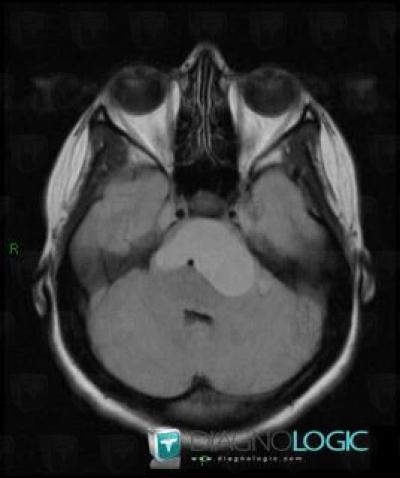

Craniopharyngiome, Hypophyse et région parasellaire, IRM

Voici les informations spécifiques à l'image clé ci dessus:

- Diagnostic Craniopharyngiome, Localisation(s) Hypophyse et région parasellaire, comportant les gammes Lésion en hypersignal T2 sellaire ou parasellaire